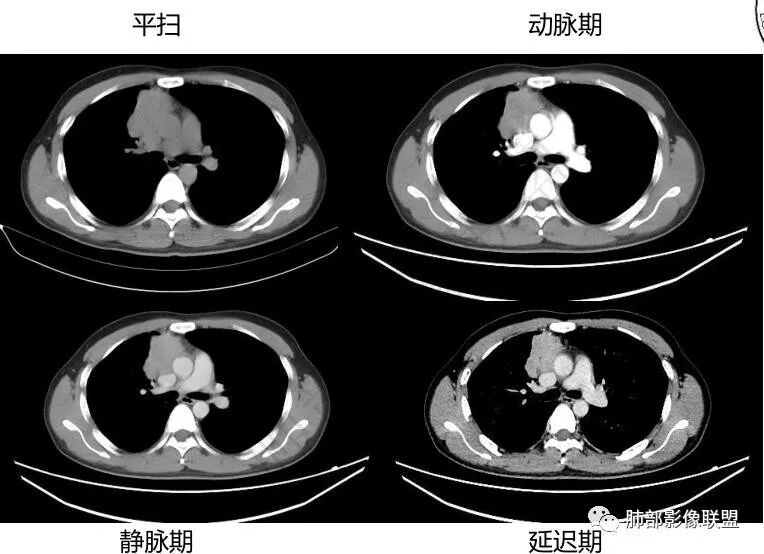

中青年男性,前纵膈偏右侧软组织肿块,形态不规则,有分叶,密度均匀,增强病灶轻中度强化,内部可见低或无强化区域,病灶与血管周围间隙分界不清晰,考虑恶性或交界性肿瘤,胸腺类癌>生殖细胞瘤>淋巴瘤。

青年男性,前上纵隔占位,渐进强化,坏死不明显,nse稍高,首先考虑类癌,鉴别精原,内胚窦瘤,需要结合实验室检查HCG,AFP等

男性32岁前纵隔偏右侧见一不规则软组织影,边缘毛刺,呈分叶征,同侧内乳动脉增粗,延迟性强化,内见条状分隔影,考虑胸腺瘤(B1、2,临界年龄段,分隔有些提示倾向),NSE轻度升高,中度强化,类癌代排。内胚窦及精原等生殖细胞肿瘤影像不符合,建议结合实验室检查

年轻男性,NSE稍高,前纵隔偏右侧不规则实性肿块,平扫密度均匀,增强渐进性不均匀强化,内见低密度区,似见条样分隔。考虑为胸腺瘤,建议实验室检查HCG,AFP等鉴别生殖细胞肿瘤

前纵隔右侧不规则软组织肿块,边缘欠清,增强渐进性强化,内见星状无强化分隔,部分分隔延迟强化,青年男性,首先考虑精原细胞瘤,鉴别胸腺瘤,NSE轻度升高,类癌也需鉴别!

胸腺瘤这个表现,起码B1期以上,不均匀小灶性坏死,边界膨隆结节凸起明显,比较硬,但是侵袭性并不算强。与周围关系,加上发病年龄比较偏小一点,胸腺瘤B期级别或更高这样是少见的,精原细胞瘤贴合度更高一些。其它生殖来源的坏死和侵犯程度基本不符合。最主要鉴别还是临床实验室,少走弯路,afp和hcg等。

前纵隔肿块,轻度分叶,边界不清楚,延迟强化,可见分隔,倾向恶性或具有一定侵袭性病灶。

一.精原细胞瘤  20-40岁 ,年轻男性多见,密度均匀,边界清楚,轻度强化,可有坏死,基本不出现钙化,HCG可升高,AFP一般不升高,侵犯血管的程度一般比淋巴瘤明显。

三.高危型胸腺瘤 年龄偏大,以中老年多见,中度或明显强化,强化幅度大于淋巴瘤,有囊变和坏死,可见钙化,胸膜转移,三分之一有重症肌无力,尤其是B2-B3型等。胸腺癌可见淋巴结转移。